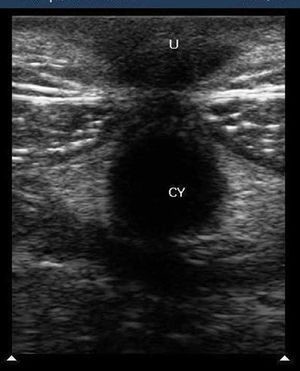

Case history: A 67-year-old female with a history of long standing goiter presented with a short onset history of cough and breathlessness. She did not have any fever or hemoptysis. The chest X-ray was unremarkable.